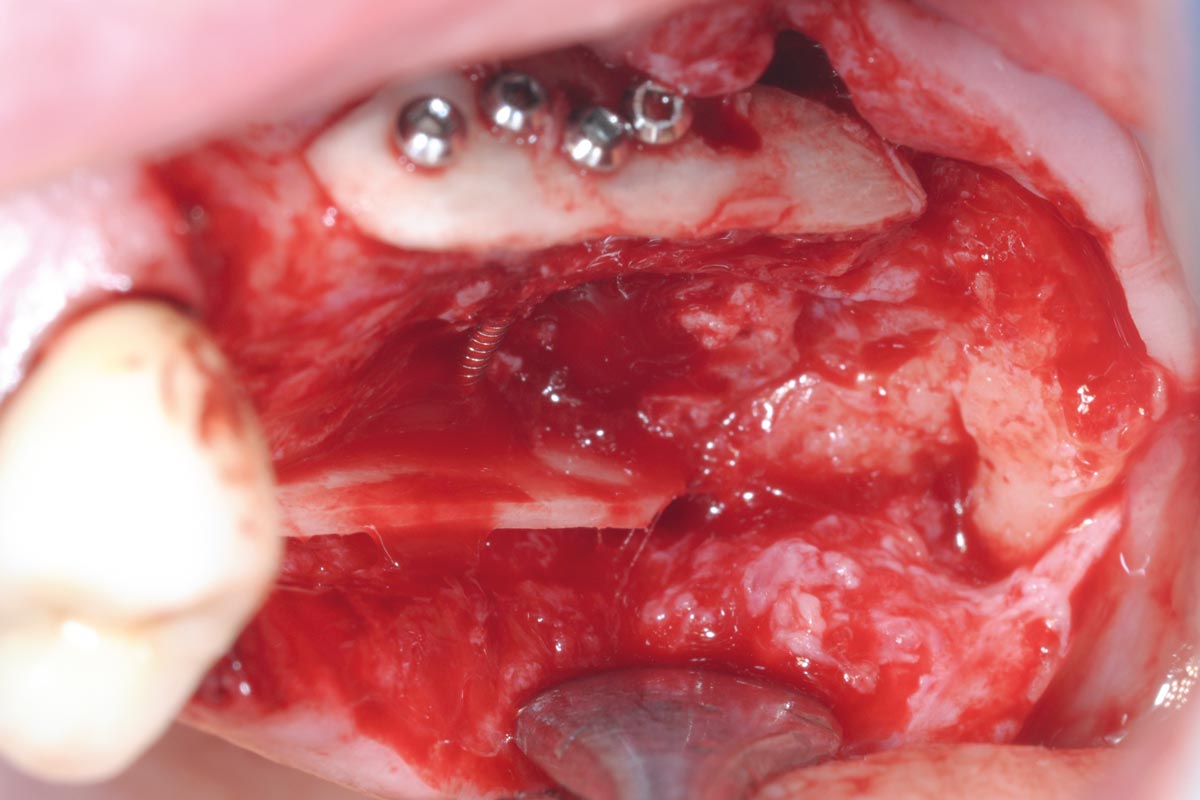

4/15 - Intraoperative view after fixation of maxgraft® cortico with a micro screw system. Placement in parallel technique to obtain a horizontal and vertical augmentationTreatment of a combined horizontal and vertical bone defect in the maxilla with maxgraft® cortico in the allogenic shell technique - Dr. R. Würdinger